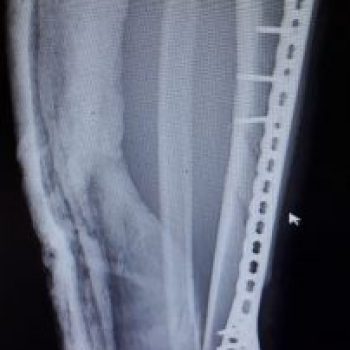

Qulfli va qulfsiz mixlar

Katta Boldir

Tibia Distal Medial – Qulfli va qulfsiz mixlar

Distal Tibia Medial